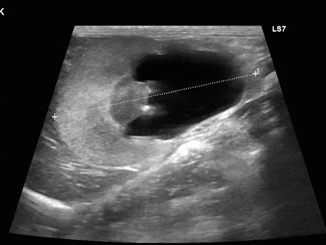

尿管結石が原因で腎臓は水腎症になっていました。

尿管結石2箇所以上閉塞による水腎症。

内科的な治療にも反応せず、SUBシステムをいれることになりました。

透視下にて腎盂に入っていることを確認。

ここにカテーテルを装着していきます。